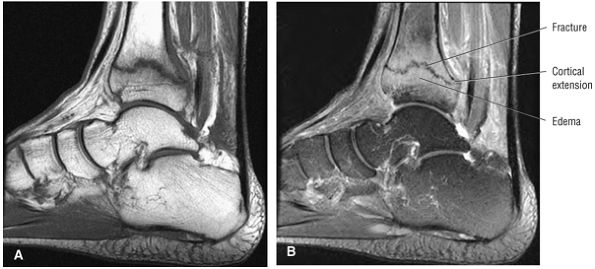

![]() |

|

FIGURE 5.28 Tibiotalar Joint.

FIGURE 5.29 Impingement.